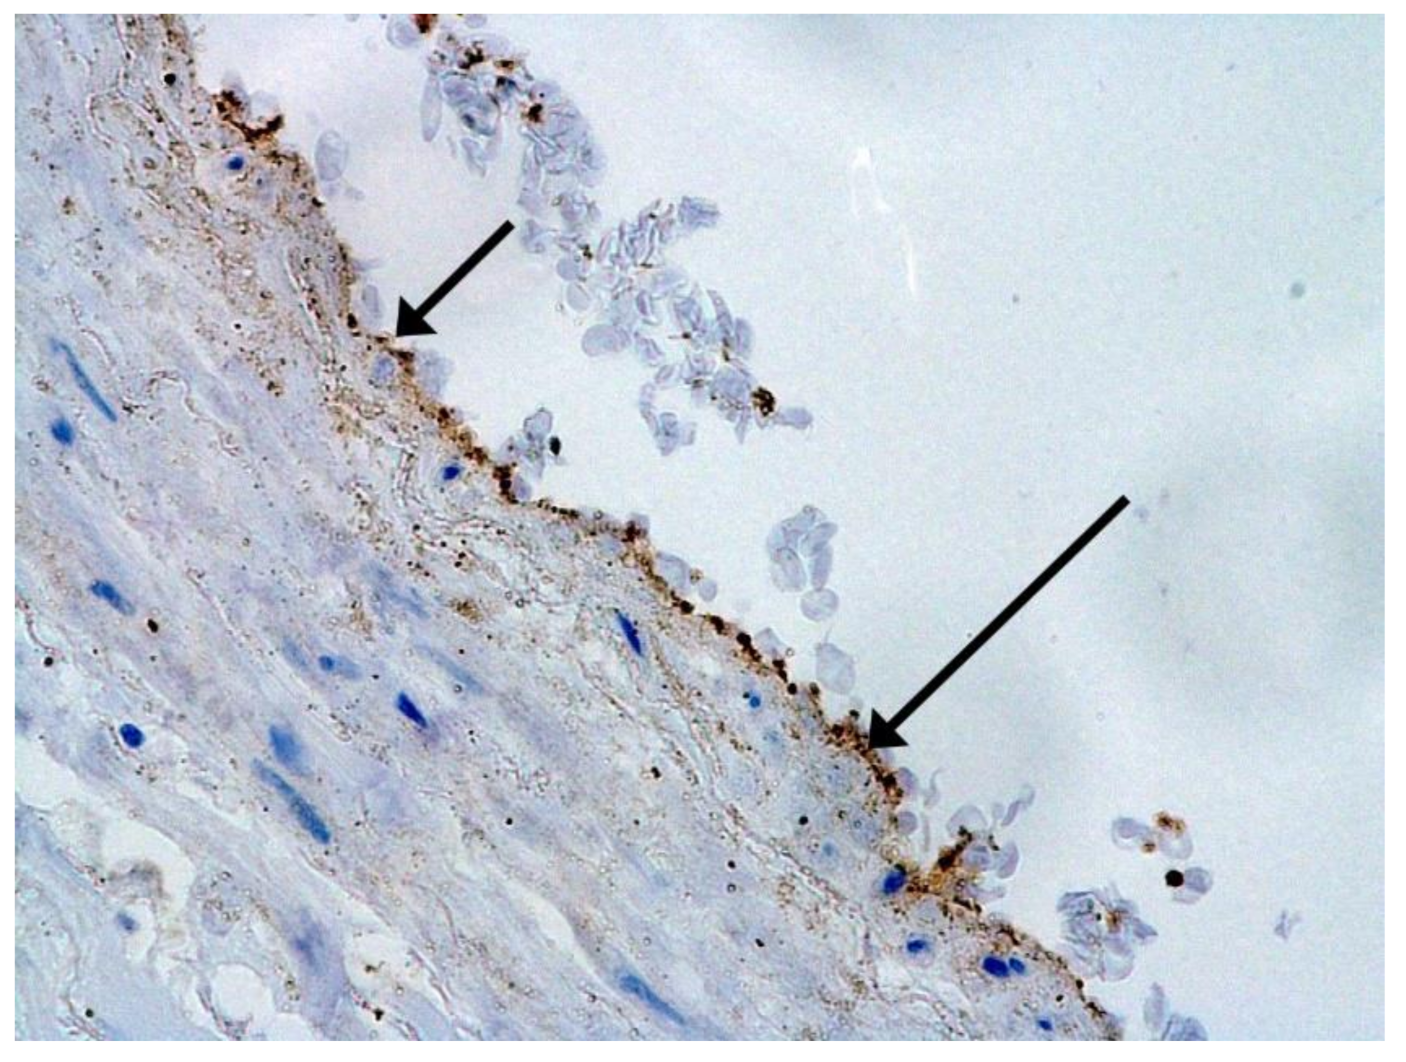

We consider certain changes to be directly related to virus propagation. We succeeded in detecting virus spike antigen in the bronchiolar epithelium (Figure 1) and macrophages (Figure 2) as well.

Spike antigen of SARS-CoV-2 in bronchiolar epithelium (arrow). IHC, ×100.

Figure 2.

Spike antigen of SARS-CoV-2 in cytoplasm of macrophages (arrows) in lung. IHC, ×200.